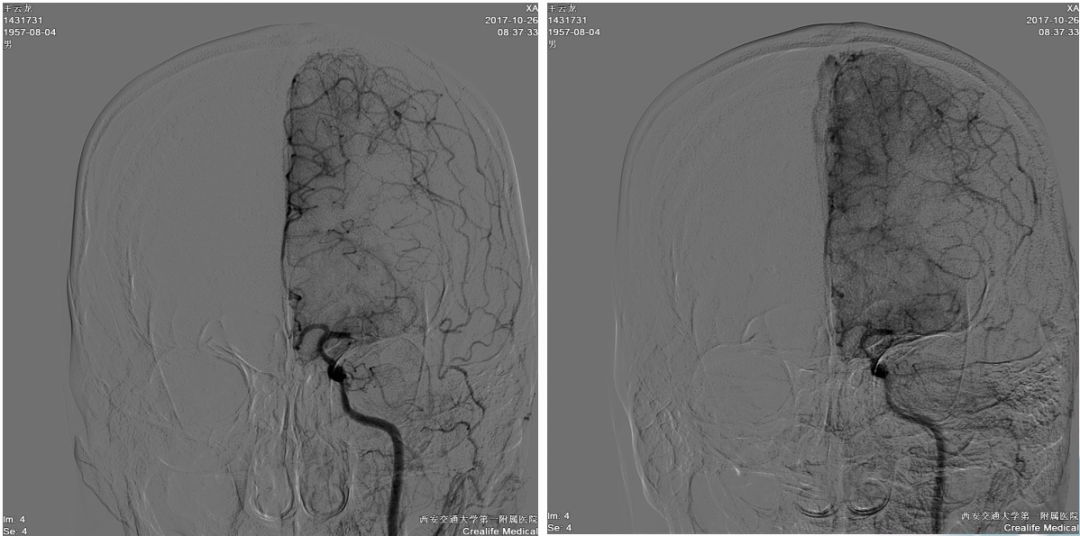

球囊扩张

微导管在血栓远端造影

支架到位释放透视图+造影图

异常早显静脉

取出栓子

术后正侧位造影图片